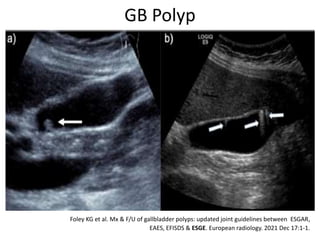

GB Polyp

Foley KG et al. Mx & F/U of gallbladder polyps: updated joint guidelines between ESGAR,

EAES, EFISDS & ESGE. European radiology. 2021 Dec 17:1-1.

Cont…..

Indn of Cholecystectomy:

>1 cm

6-9 mm polyp with 1 of following risk of Mg-:

 Age> 60

 PSC

 Asian

 Sessile polypoid lesion with focal GB wall thickening > 4mm.

6-9 mm /< 5 mm without risk of Mg:

 F/U USG- 6 mons, 1 yr & 2 yrly

 Discontinue F/U > 2 yrs in absence of growth.